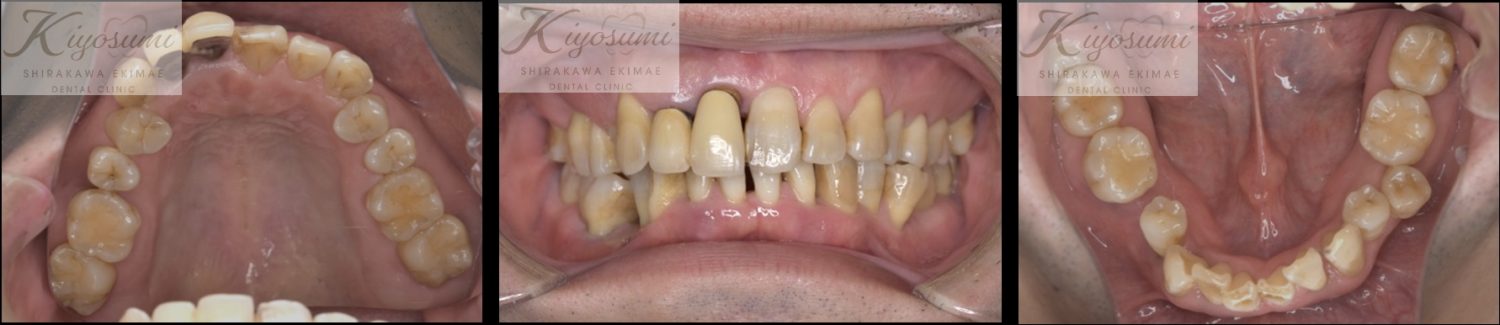

| 主訴 | 歯が揺れて噛めないので、噛めるようにして欲しい。 |

| 治療内容 | 基本的な歯周病治療、根の治療を実施し、歯の高さが足りない箇所は歯冠長延長術、保存が難しい歯は一部歯根分割抜去を行いました。欠損部はインプラントを用いず、ジルコニアブリッジで仕上げています。 |

| 想定されたリスク | ※残存している歯の本数が少ないため、残っている歯だけでブリッジを行うには長期予後が見込めない可能性があり、患者さんにご理解をいただいたうえで被せ物を行っています。 ※歯周病治療や根の治療をしても歯を残せない可能性がありました。 |